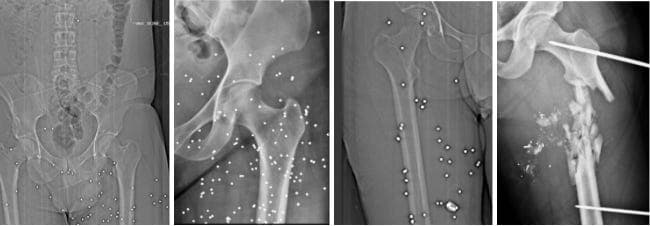

In severe pelvic and femur fractures, physicians warned of possible damage to major blood vessels, including the femoral artery, with life-threatening bleeding.

Four cases of pelvic, thigh, and hip injuries: in three images, multiple shotgun pellets are scattered through the soft tissue around the pelvis and thigh, and in one image, there is severe destruction with a comminuted fracture of the femur accompanied b